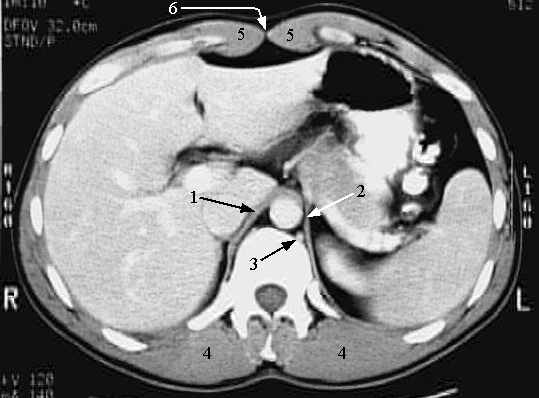

Abdomen - Abdomen Cross 2:

1. Right crus of the diaphragm

2. Left crus of the diaphragm

3. Hemiazygos vein

4. Erector spinae muscle

5. Rectus abdominis muscle

6. Linea alba